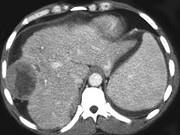

问题 女,47岁,曾患乙肝,现右上腹及肝区疼痛、腹胀,消瘦乏力半月,AFP阳性,CT扫描如图,请选择最可能答案()

选项 A.肝癌 B.肝血管瘤 C.肝脓肿 D.肝转移瘤 E.肝包虫病

答案 A